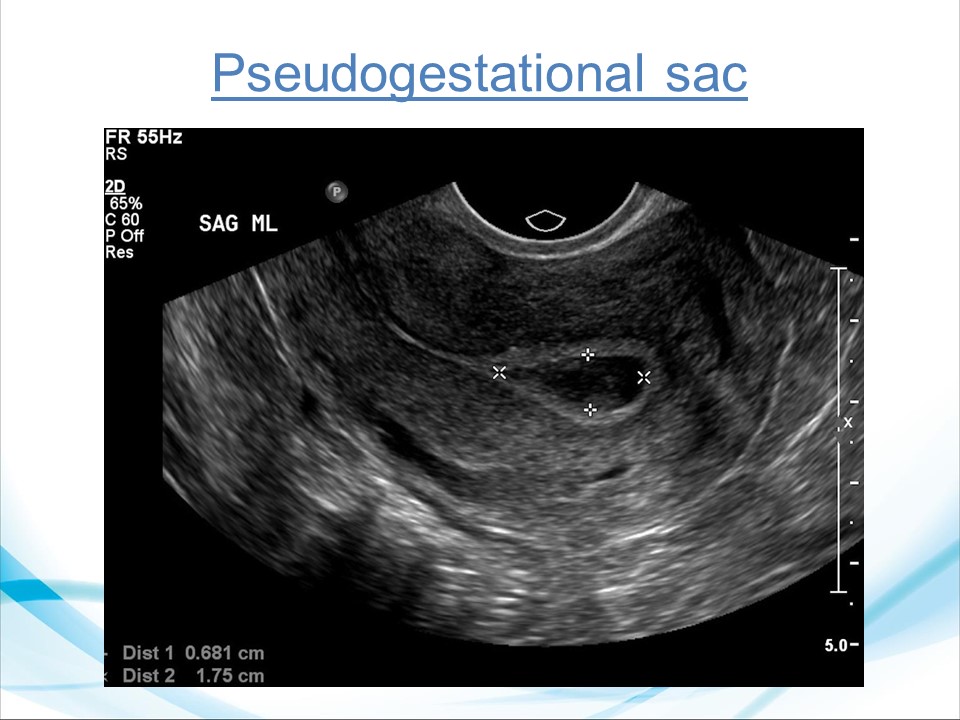

Siêu âm đánh giá khả năng sống của thai giai đoạn sớm

BS. CKI Phạm Thị Phương Anh - BV Mỹ Đức